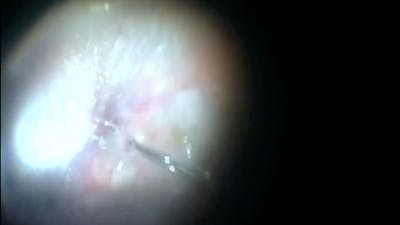

The RETINAWS panel led by Kourous Rezaei, MD, discuss techniques for vitreoretinal surgery and rare surgical cases.